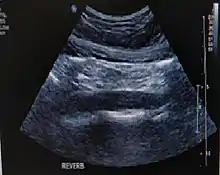

In medical imaging, artifacts are misrepresentations of tissue structures produced by imaging techniques such as ultrasound, X-ray, CT scan, and magnetic resonance imaging (MRI). These artifacts may be caused by a variety of phenomena such as the underlying physics of the energy-tissue interaction as between ultrasound and air, susceptibility artifacts, data acquisition errors (such as patient motion), or a reconstruction algorithm's inability to represent the anatomy. Physicians typically learn to recognize some of these artifacts to avoid mistaking them for actual pathology.

In ultrasound imaging, several assumptions are made from the computer system to interpret the returning echoes. These are: echoes originate only from the main ultrasound beam (while there are side lobes and grating lobes apart from the main ultrasound beam); echoes returns to transducer after a single reflection (while an echo can be reflected several times before reaching the transducer); depth of an object relates directly to the amount of time for an echo to reach the transducer (while an echo may reflect several times, delaying the time for the echo return to the transducer); speed of ultrasound in human tissue is constant, echoes travel in a straight path. and acoustic energy of an echo is uniformly attenuated. When these assumptions are not maintained, artifacts occur.[4]